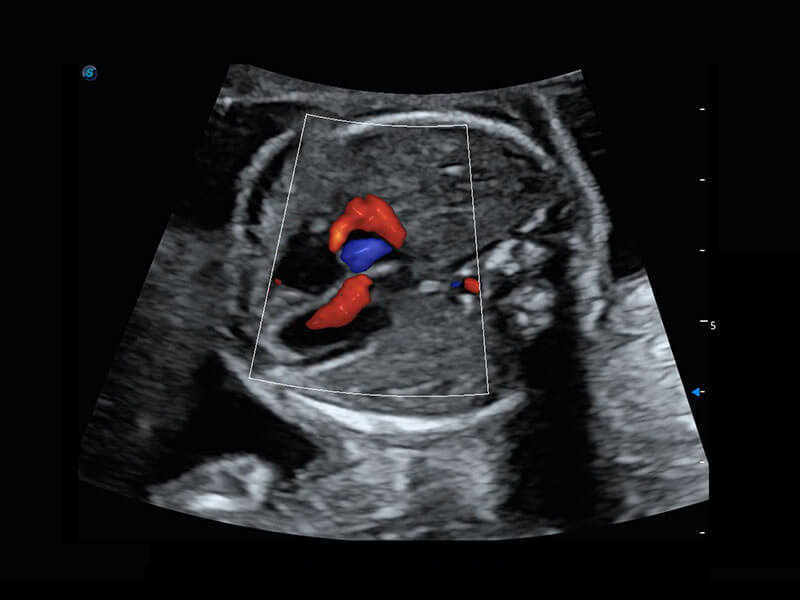

P60搭载一系列胎儿心脏成像技术,实现精细的胎儿心脏评估。

四腔切面

四腔心血流